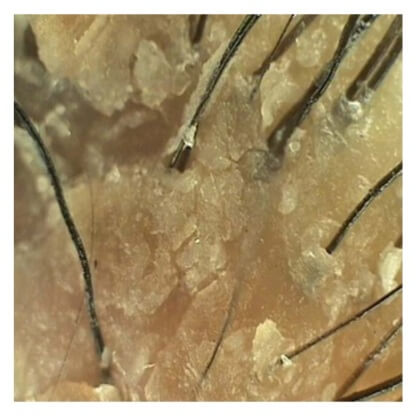

지성 비듬은 각질과 피지가 덩어리가 되어서 두피에 잔류하고 있는 상태로 입자가 크고 무게감이 있기 때문에 쉽게 떨어지지 않고 문제성 두피를 만들 수 있는 비듬이다

모공이나 두피 부근에 각질이 심하게 붙어 있고 마치 물결모양처럼 겹겹이 쌓여 있는 것을 볼 수 있다

비듬 흡착으로 큐티클 손상과 함께 굴곡 있는 상태의 모발로 보이며 심한 악취가 발생한다. 갑자기 발생된 비듬으로 모발 밀도 감소와 모발 굵기의 연모화 현상이 일어나게 된다